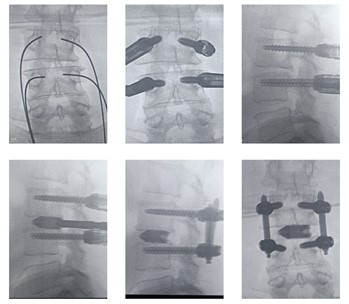

1. Endoscopic decompression and percutaneous screw and rod fixation: In endoscopic decompression, the ligamentum flavum, disc and facet is targeted directly without damaging the surrounding tissues with help of specialised camera system called endoscopes. It is least invasive form of decompression. After decompression is done, very small incisions are given to put screws and rods in the spine, thereby fixing the spine and overcoming instability. There are minimum incisions, few stitches, minimum blood loss, early rehabilitation and quick recovery. Collateral tissue damage is minimum amongst all the techniques of decompression and fixation therefore long term pain relief is best.

We perform a fully endoscopic decompression of the neural structures using trans-foraminal or inter-laminar technique whichever is suitable for the patient.

Stability of spine is achieved with percutaneous screw and rod stabilisation of spine.

We strongly avoid open surgery of Spondylolisthesis to enable early recovery of our patients.